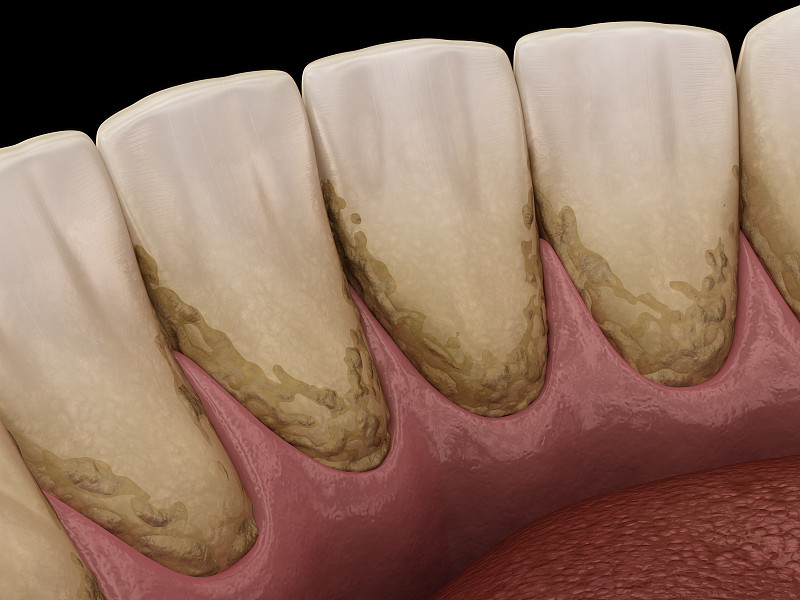

龋齿详情